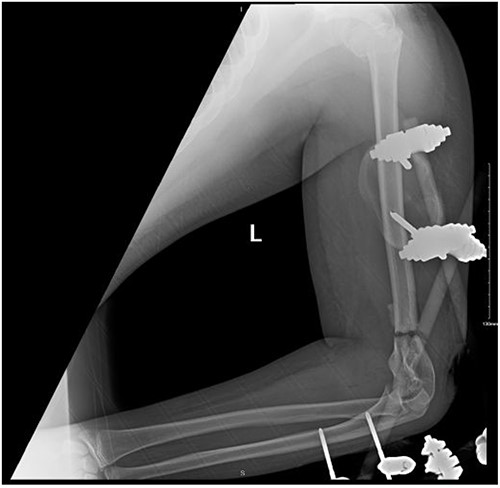

Upon arrival the patient underwent exploratory laparotomy followed by irrigation and debridement of both femur and humerus and application of external fixators (Fig. 2). The patient was admitted to the intensive care unit (ICU). Two days later, the patient underwent open reduction and internal fixation of both proximal and distal humerus (Fig. 3).

Anteroposterior (AP) view of the left humerus and elbow after Ex-fix application.